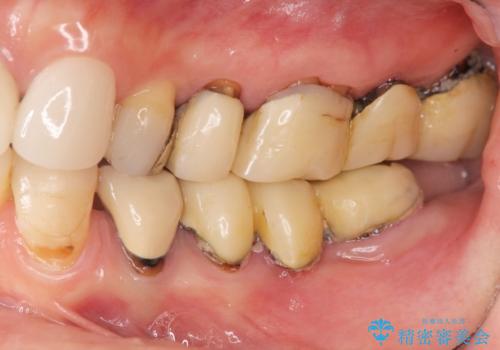

全顎 虫歯 インプラント治療

- 長年悩んでいる歯の見た目や欠損を全て治療したい、と希望され来院されました。

不適合やすり減ったクラウンを全て除去し、虫歯を丁寧に除去したのち精密なセラミック治療を行いました。

しっかりと調整された咬合関係と、見た目の改善に大変喜んでいただくことができました。